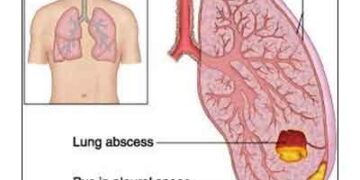

Read moreDR. JALAL MOHASIN UDDIN, আমরা শরীরের উপরি ভাগে বিশেষ করে চামড়ার বিভিন্ন অংশে ফোঁড়া হতে দেখি, যেমন- থাকে টনটনে ব্যাথা তেমনি থাকে কাঁপুনিসহ বুকে ফোঁড়া হলে কিংবা পুঁজ জমলে অনেকটা এই ধরণের লড়্গণের প্রকাশ পায়। ফুসফুসে ফোড়া হলে লড়্গণগুলি নিম্নরূপ : 1. উচ্চ তাপমাত্রার জ্বর (>103 ডিগ্রী ফারেনহাইট) হয়। জ্বর শীত করে কেঁপে কেঁপে আসে। 2. কাশি হয়ে থাকে, কাশির সাথে প্রচুর কফ বের হতে থাকে। কফ হয়ে থাকে ঘন, হলুদ এবং দূর্গন্ধযুক্ত। মাঝে মাঝে কফের সাথে রক্ত আসতে পারে। 3. রোগীকে দেখতে খুবই অসুস্থ ও দুর্বল মনে হয়। বিভিন্ন কারণে বুকে ফোঁড়া হতে পারে যেমন :- 1. নিউমোনিয়ার চিকিৎসা সময় মত করা না হলে। 2. মুখের জীবাণু যুক্ত লালা শ্বাসণালীতে চলে গেলে। 3. শ্বাসণালীতে বাইরের কোন বস্তু ঢুকে আটকে গেলে। 4. যারা তাদের শিরায় বিভিন্ন রকম নেশা জাতীয় দ্রব্য নেয়, তাদের ড়্গেত্রে বিভিন্ন জীবাণু, রক্ত দ্বারা বাহিত হয়ে ফুসফুসে যেয়ে ফোঁড়া তৈরি করতে পারে। কাদের ফোাঁড়া হওয়ার সম্ভাবনা বেশী ? 1. যাদের মুখ গহ্বর, দাঁত ও দাঁতের মারি রোগাক্রানত্ম কিংবা অপরিষ্কার। 2. যাদের ডায়বেটিস অনিয়ন্ত্রিত। 3. যাদরে পূর্ব থেকেই ড়্গতিগ্রসত্ম ফুসফুস রয়েছে, প্রভৃতি। ফোঁড়া হতে বাঁচার উপায়- 1. মুখ গহ্বর, দাঁত ও মাড়ির যত্ম নেয়া।...